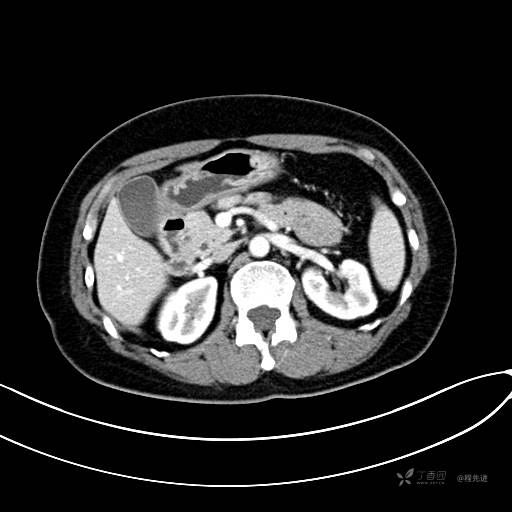

CT增强门脉期